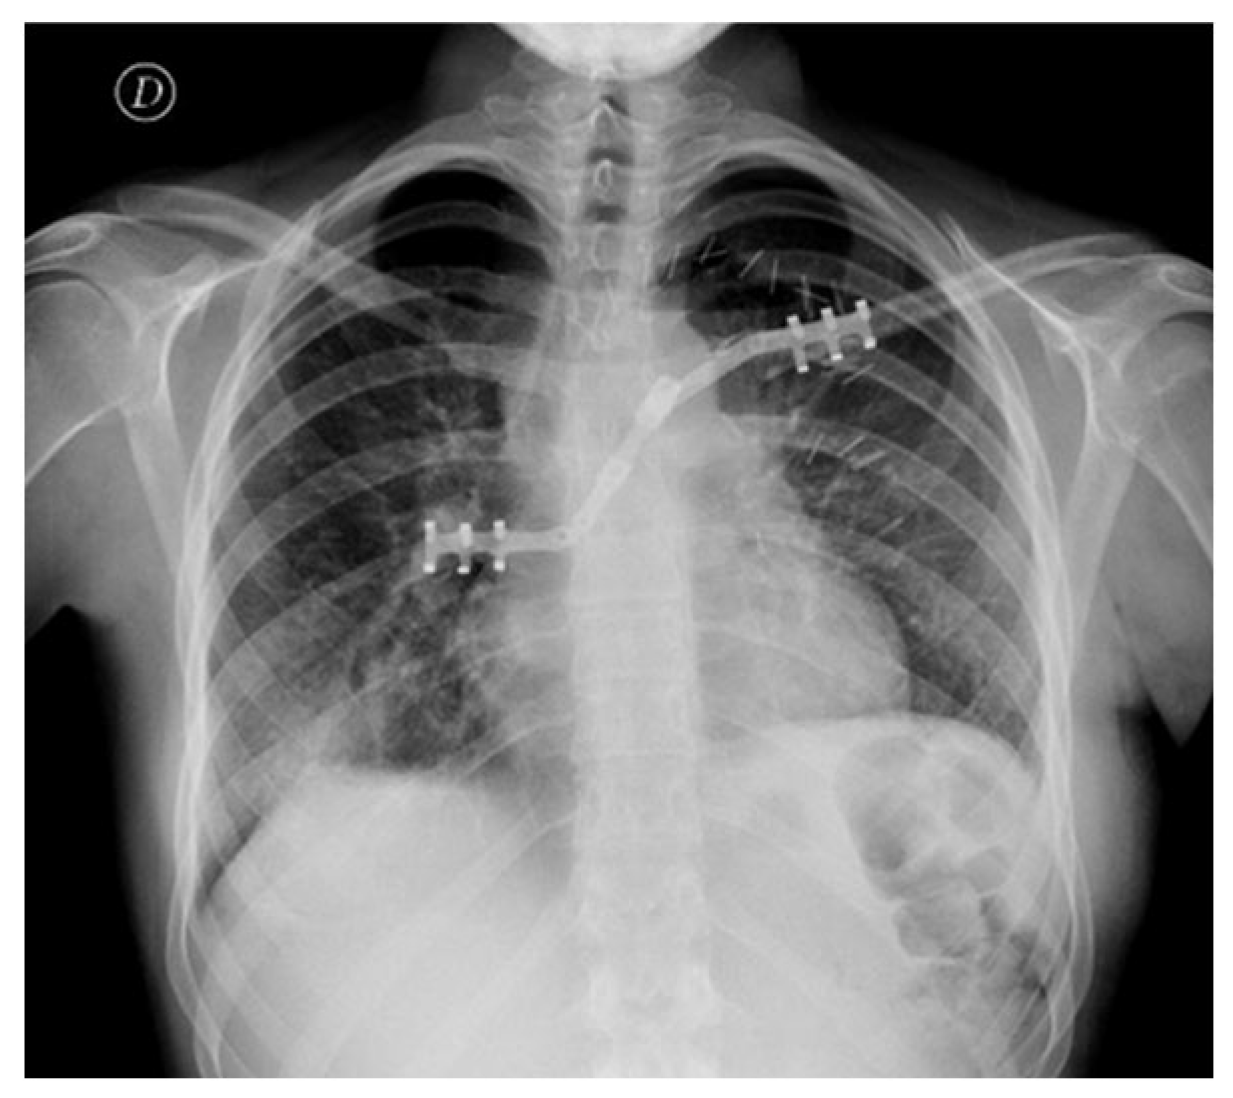

Postoperative Course

The patient recovered uneventfully and was discharged on postoperative day 7 with minimal pain and preserved shoulder mobility (Figure 3). The postoperative functional outcome was excellent. One month after surgery, the patient had regained full autonomy in daily activities without assistance (Figure 4). She subsequently received adjuvant chemotherapy with ifosfamide, after which she developed grade 4 afebrile neutropenia, grade 3 thrombocytopenia, and grade 3 anemia (Common Terminology Criteria for Adverse Events, CTCAE). She then initiated mifamurtide therapy, administered twice weekly for the first 12 weeks, followed by 48 weekly cycles. At the 6-month follow-up, with no local recurrence, stable hardware positioning and no implant migration, the patient demonstrated an almost complete range of motion, with only a minimal, functionally acceptable reduction in muscular strength. Range-of-motion testing demonstrated 170° of forward flexion, 160° of abduction, and preserved internal and external rotation, indicating near-complete recovery of shoulder mechanics. No winging, instability, or hardware irritation was observed on clinical evaluation. Objective functional assessment at 6 months further supported the favorable outcome, with a Constant–Murley score of 88 points and a Disabilities of the Arm, Shoulder and Hand (DASH) score of 7.5, indicating excellent shoulder function with minimal residual disability.

Figure 3. Postoperative chest X-ray showing correct alignment and fixation of STRATOS.